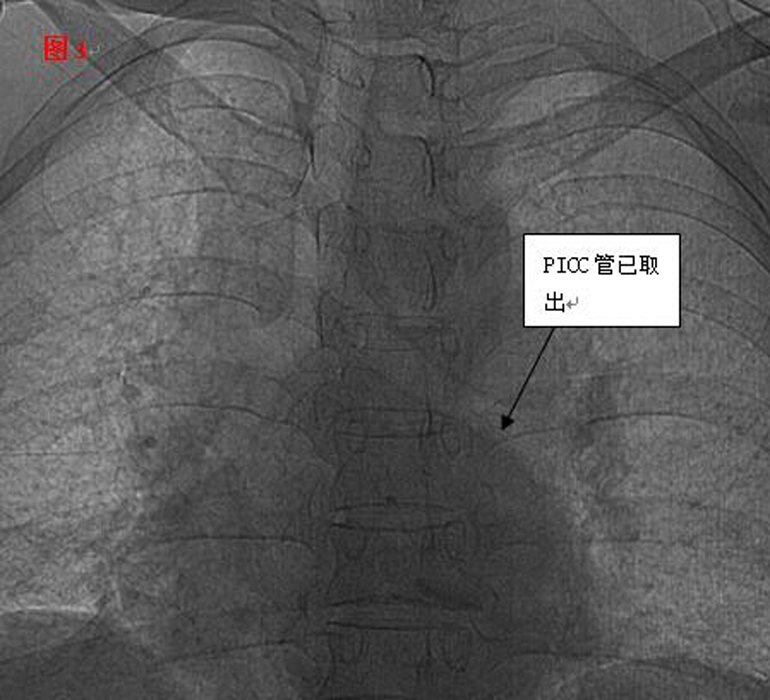

??? 憑借醫(yī)師的高超技術(shù)加上團(tuán)隊(duì)的密切合作,手術(shù)圓滿(mǎn)成功,30厘米的導(dǎo)管被完整取出,術(shù)后復(fù)查未見(jiàn)殘留。當(dāng)手術(shù)結(jié)束的那一刻,躺在手術(shù)臺(tái)上的麗琴由衷的感謝聲,以及在場(chǎng)觀(guān)摩學(xué)習(xí)人員的掌聲,讓手術(shù)室內(nèi)格外溫情。